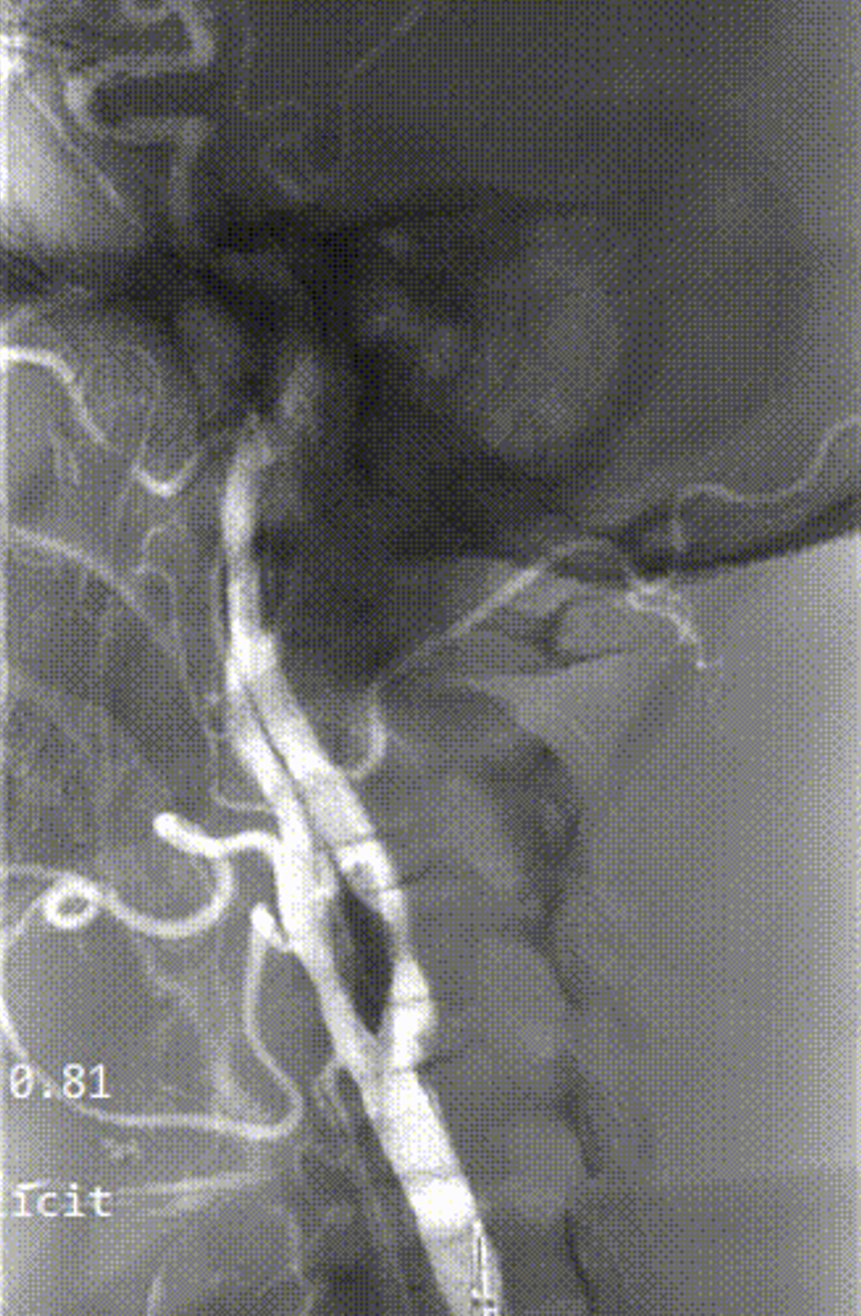

病例1:61岁男性,因双下肢间歇性跛行检查发现双侧颈动脉狭窄,冠脉情况严重,先行两次PCI,后行双侧CAS,先左后右,术后恢复良好。

左侧术前

左侧术后